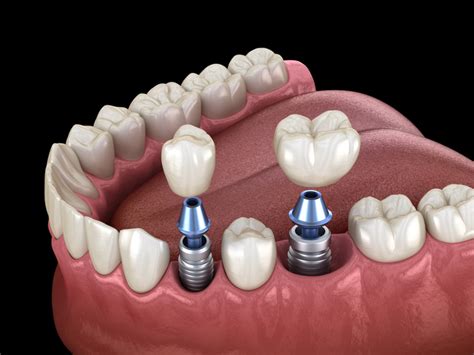

- Implantes Dentales: Si la extrusión es causada por la falta de un diente antagonista, la colocación de un implante dental puede ser la solución ideal. Un implante dental reemplaza la raíz del diente perdido y proporciona soporte para una corona, restaurando la función y la estética.

Los implantes dentales son una excelente opción para reemplazar los dientes perdidos. Ofrecen varias ventajas:

- Preservación del Hueso: Los implantes ayudan a preservar el hueso alveolar, evitando la atrofia que se produce tras la pérdida de un diente.

- Estabilidad: Los implantes proporcionan una base sólida y estable para la corona, restaurando la función masticatoria y la estética.

- Durabilidad: Con un cuidado adecuado, los implantes pueden durar muchos años.